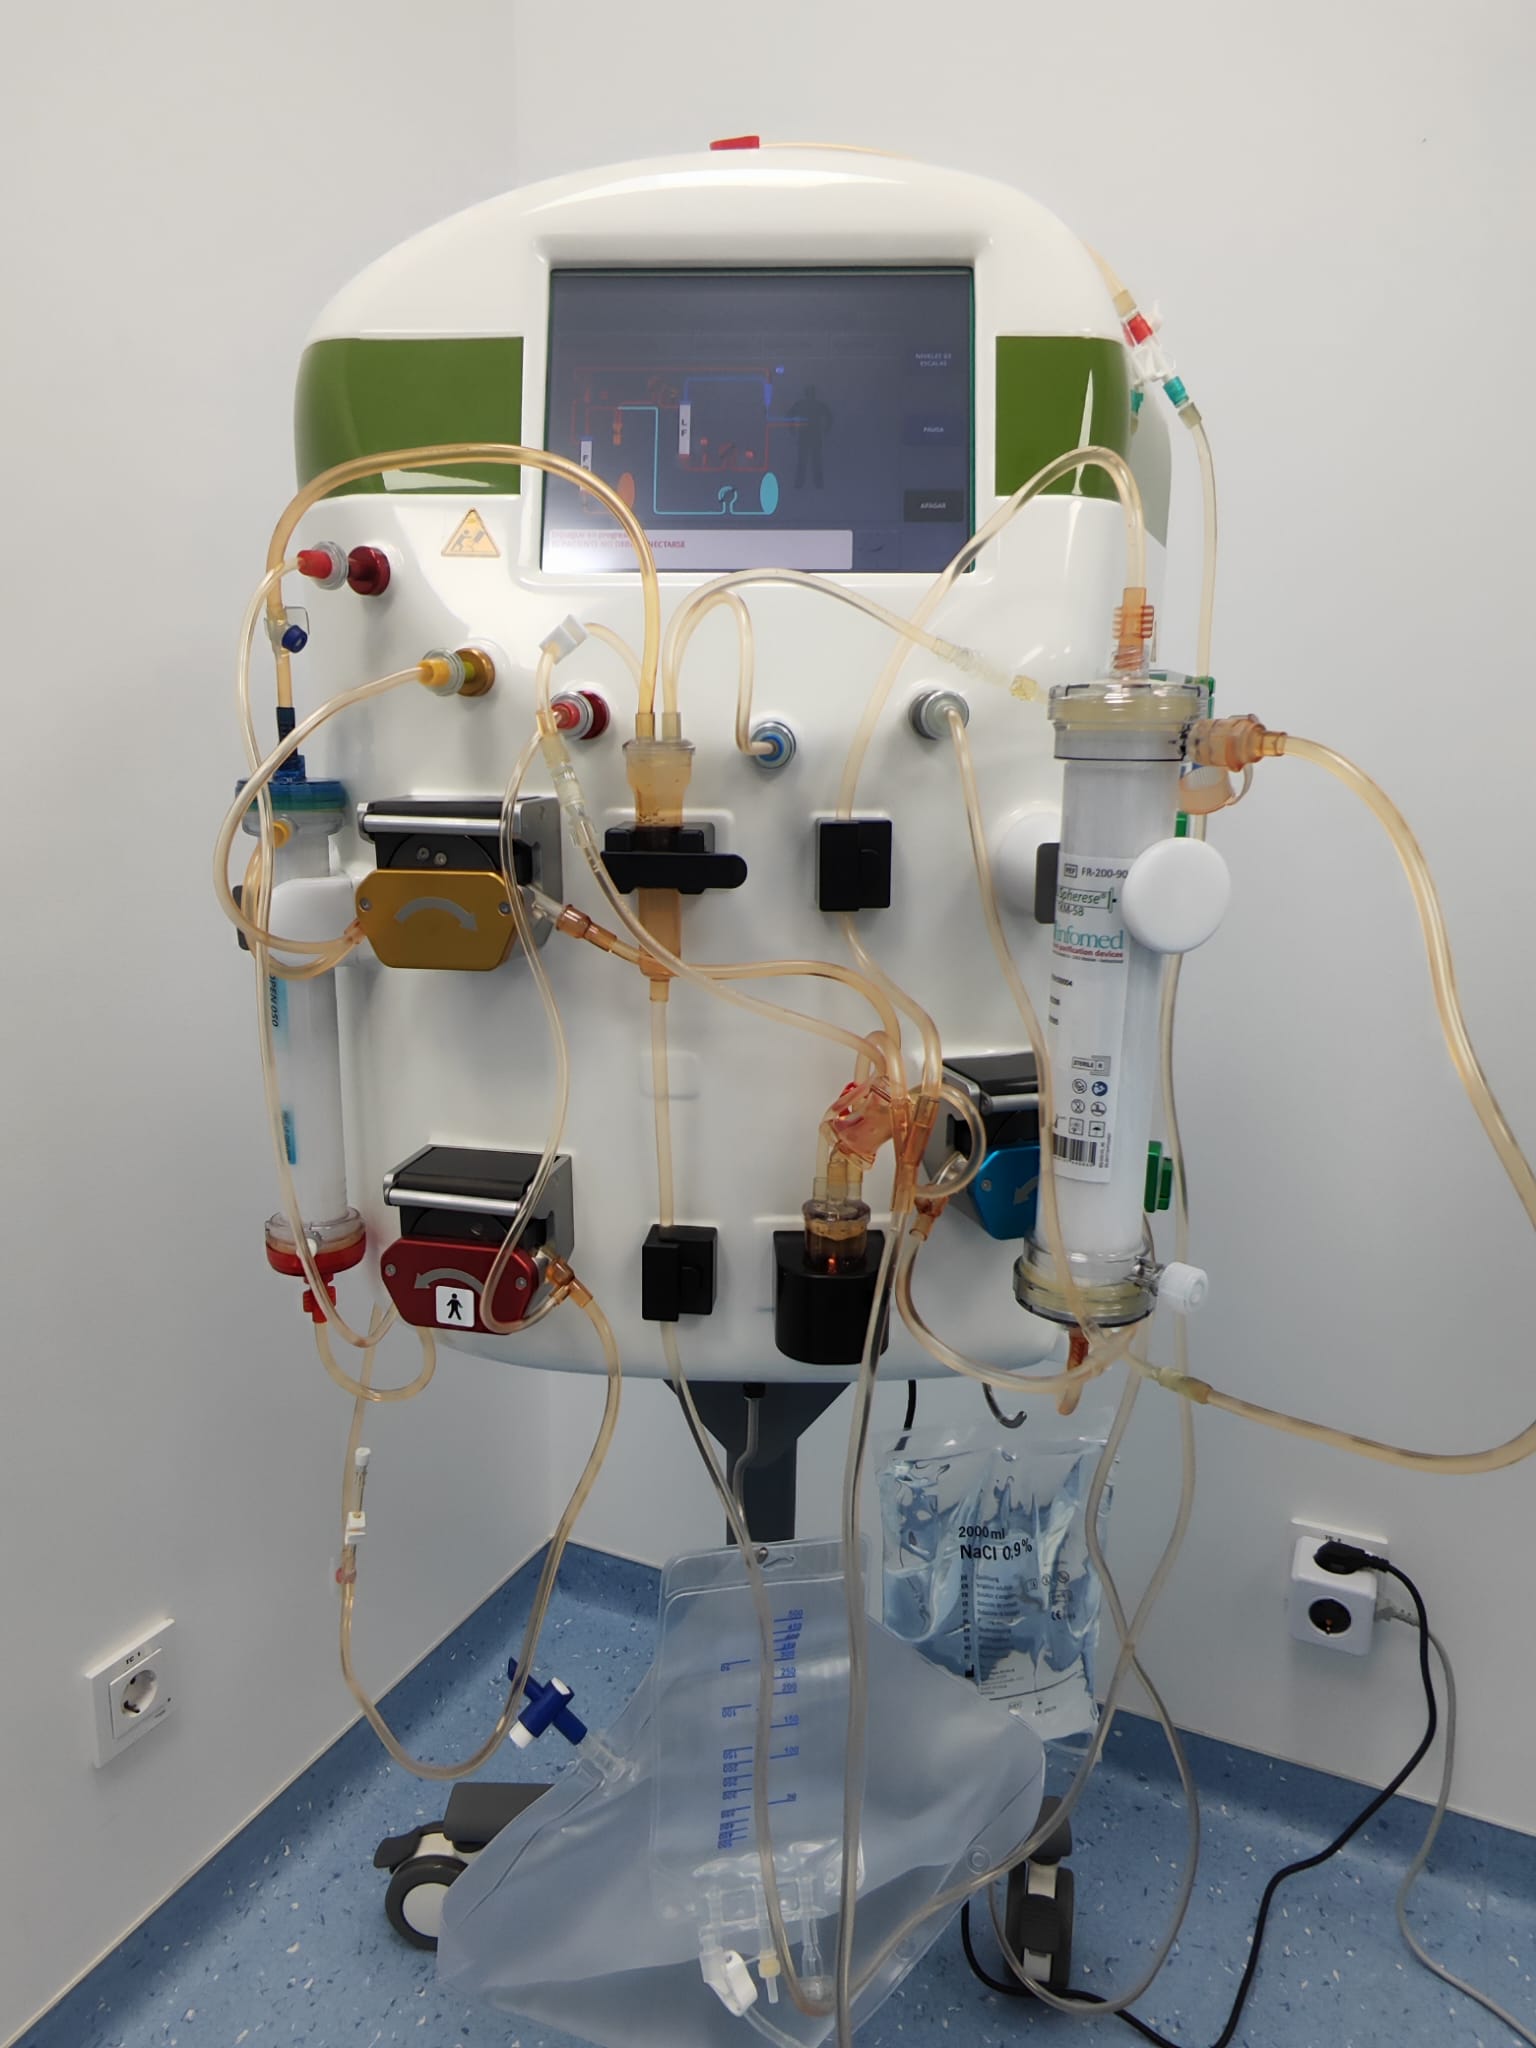

Este tratamiento limpia tu sangre de toxinas y todo tipo de sustancias nocivas y rejuvenece tus células y tejidos La